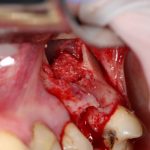

Через 3 месяца — вторая операция — установка имплантата в сформированный объем костной ткани:

Как видите. восстанавливается всё очень легко, никаких дефектов не остаётся, но при этом мы получаем важное преимущество: достаточную свободу движений при формировании субантральной полости и хороший визуальный контроль за состоянием слизистой оболочки. Никакая нажопная оптика или суперпупермикроскоп, к сожалению, не обеспечат подобный контроль при закрытом синуслифтинге. Да, операция получается травматичнее и масштабнее, чем «закрытый» синуслифтинг, но несёт в себе гораздо меньше рисков.